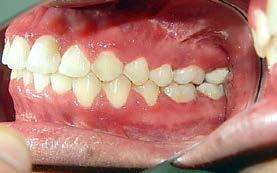

Figura 3. Lateral derecha. Figura 4. Izquierda de inicio. Figura 5. Frente. Figura 6. Overjet, laterales derecha e izquierda.

Las fotografías intraorales muestran las relaciones molares clase II y las relaciones caninas clase II bilaterales (Figura 3 y 4), espaciamiento anterosuperior, un overjet y overbite aumentado (Figura 5). La forma de los arcos es cuadrada, superior e inferior, con el apiñamiento moderado inferior y los espacios en superior.